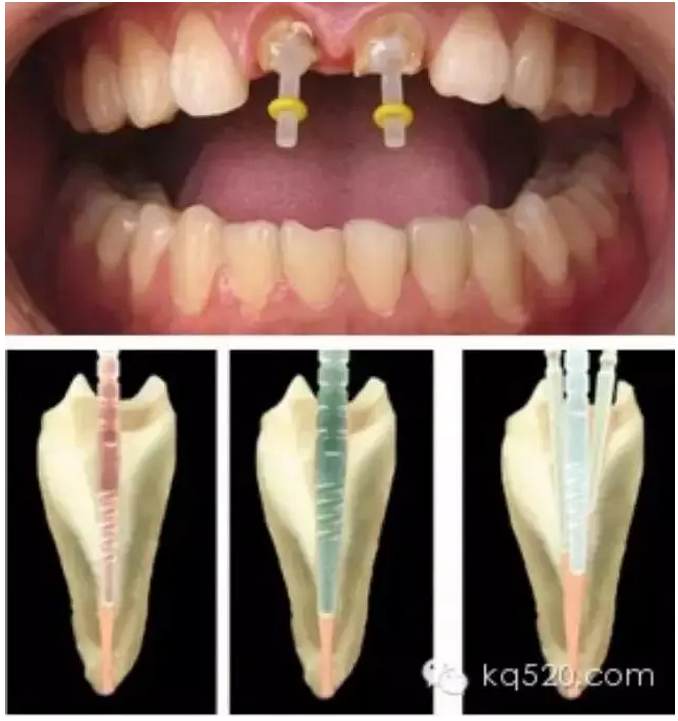

前面我們講過,牙齒內(nèi)部實(shí)際上是一個(gè)空腔,這個(gè)空腔我們稱之為“根管系統(tǒng)”。同單純的“爛神經(jīng)”相比,“根管治療”不僅僅是要將“根管”中的牙髓“殺死”,還要將牙髓從“根管”中清除出來,然后要進(jìn)行徹底清理和嚴(yán)格消毒,并用人工的充填材料將“根管”嚴(yán)密填塞。這就是所謂的“根管治療”。一個(gè)“根管治療”做得是否完善,會(huì)在很大程度上決定了這顆牙齒的壽命。而且,不僅僅是對(duì)于牙髓炎,牙齒的其他疾?。ㄈ绺庵苎椎龋┮残枰捎酶苤委煹姆椒ú拍艿玫街斡膫鹘y(tǒng)的根管治療三部曲(即根管預(yù)備、根管消毒和根管充填)來講,一般的根管治療需要三次。但是這僅僅是理論上的情況,實(shí)際上因患者而異,因牙而異,因醫(yī)生的技術(shù)水平而異?,F(xiàn)代根管治療技術(shù)有了飛躍性的發(fā)展,有些根管治療甚至可以一次完成。